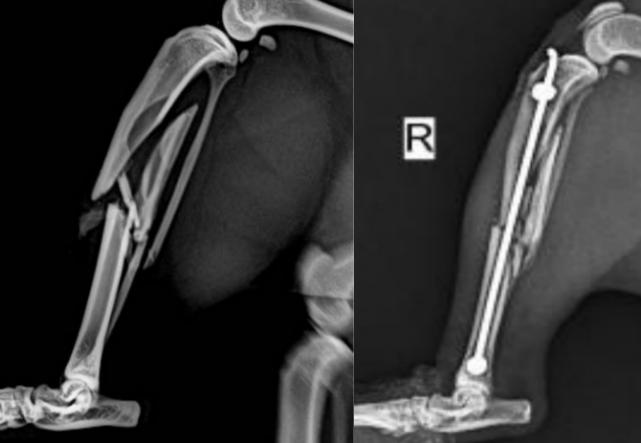

外固定器固定是治療骨折時常見的固定方式之一,醫(yī)生通常根據(jù)經(jīng)驗選擇外固定的類型、安裝位置及Schanz釘?shù)臄?shù)量,當固定方案不合理時會造成外固定的穩(wěn)定性差甚至導(dǎo)致Schanz釘斷裂。

通過逆向工程和3D打印技術(shù)相結(jié)合重構(gòu)骨折患者的1:1的脛骨骨折模型,采用XTDIC三維全場應(yīng)變測量系統(tǒng)對Orthofix單邊外固定器的整體變形進行精確的測量,以便探索更加合理的、個性化的固定方案,為醫(yī)生制定手術(shù)方案提供依據(jù)。

外固定器固定脛骨示意圖